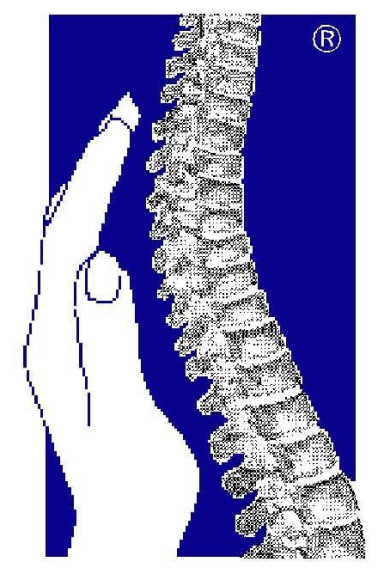

"Wir machen Sie mobil, denn Bewegung ist entscheidend für Ihr Leben und Ihre Lebensqualität!"